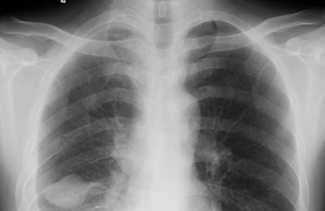

摘要:醫(yī)學影像學中用大量“概念”在日常工作中頻頻使用,一些概念的定義、內涵較為熟悉,但用相當多的概念使用者只有含糊的理解,特別是隨著科學的發(fā)展,很多概念的內涵不斷更新

醫(yī)學影像學中用大量“概念”在日常工作中頻頻使用,一些概念的定義、內涵較為熟悉,但用相當多的概念使用者只有含糊的理解,特別是隨著科學的發(fā)展,很多概念的內涵不斷更新,一些新的內涵被引用、一些被揚棄、一些被優(yōu)化、一些被限定。面對這些動態(tài)變化的概念,醫(yī)學影像學醫(yī)生和技師若不能及時地掌握其精確地定義和內涵,則必然會影響對知識的理解和應用。